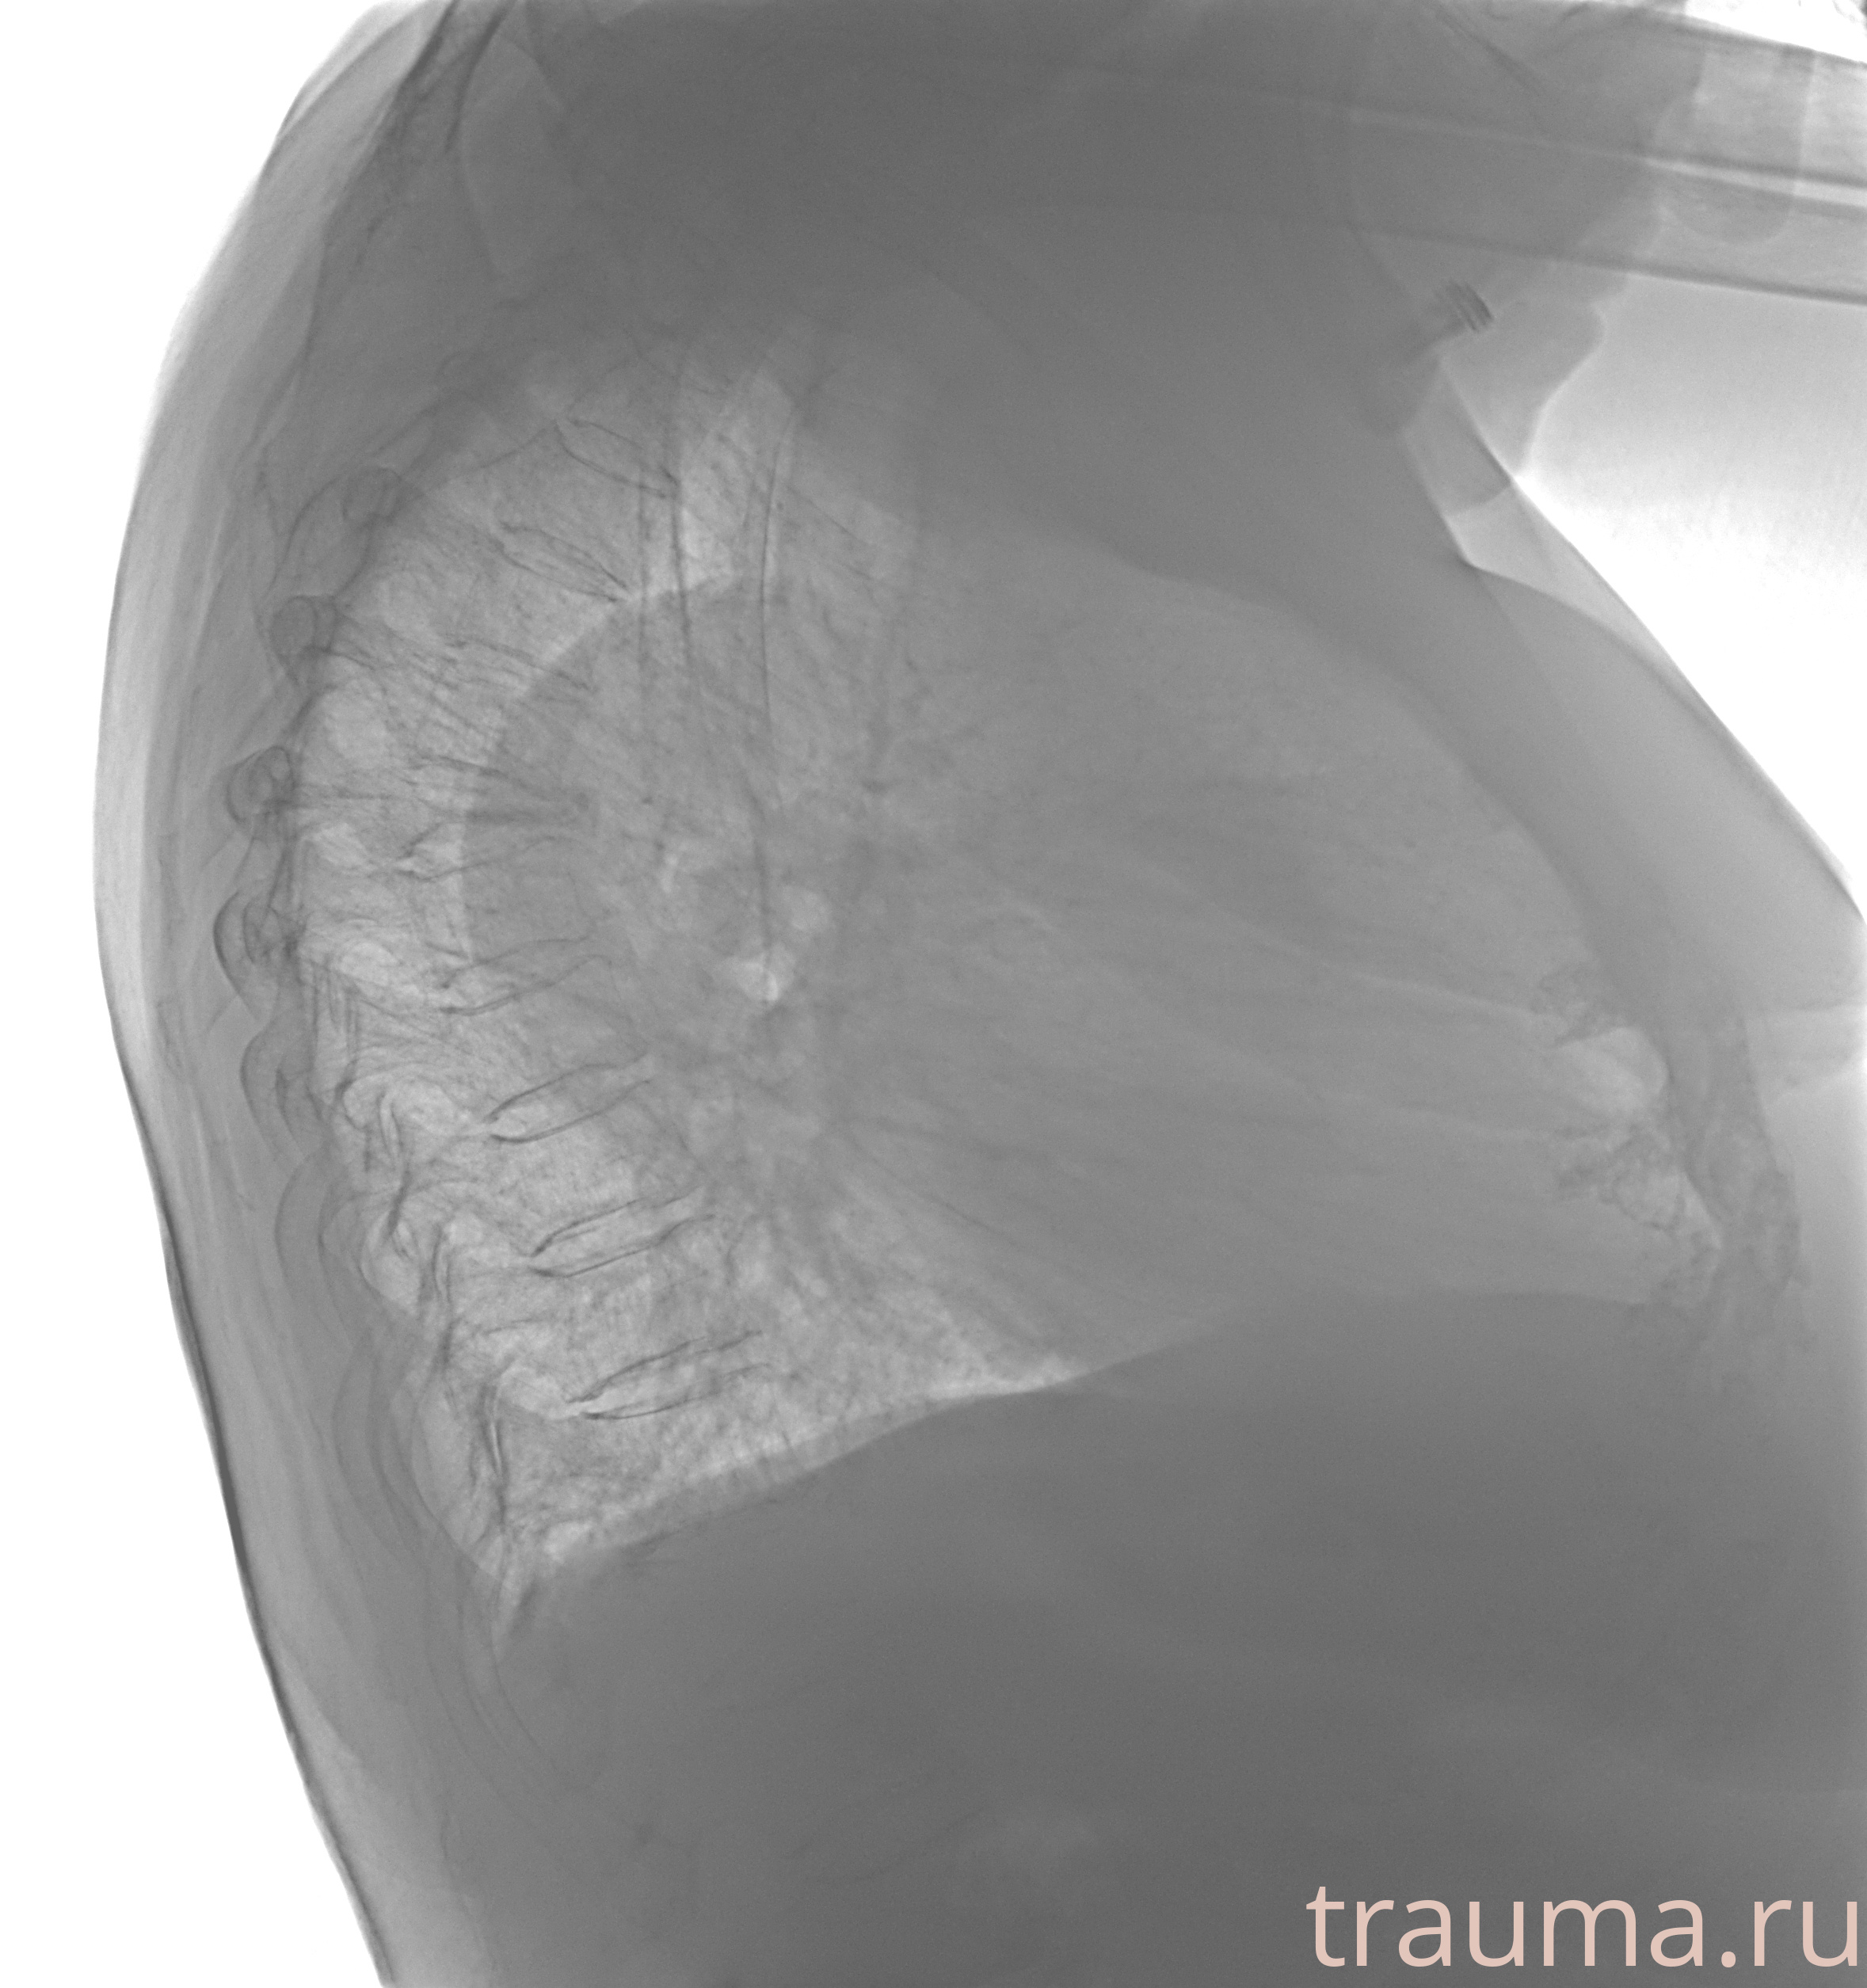

Рентген на дому: по вашему адресу приезжает врач-рентгенолог, травматолог-ортопед с мобильным рентгеновским аппаратом, проводит диагностику травмы или заболевания, делает необходимые рентгенограммы, дает рекомендации по дальнейшему лечению. Получить качественные снимки в домашних условиях возможно благодаря уникальной методике, разработанной МосРентген Центром для института  Склифосовского

при переломе шейки бедра и пневмонии от компании МосРентген Центр - партнера Института имени Склифосовского